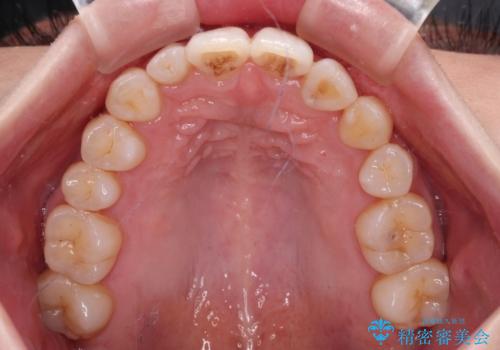

補助装置を併用したインビザラインでの八重歯の抜歯矯正

- 八重歯と奥歯の咬み合わせを気にして来院された患者様です。

インビザラインによる矯正治療を希望されたため、八重歯改善のための抜歯矯正部分は補助装置を併用し、その後はインビザラインにて行うこととしました。

下顎の右側変位が顕著であったため、ワイヤー矯正の方が咬み合わせは改善しやすいのですが、ある程度は時間がかかっても良いとのことであったので、インビザラインにて矯正治療を行うこととしました。

骨格的に下顎が右側に変位していたため、上下正中を合わせることは困難であることは分かっていました。それでも、なるべく合わせるようにとしたため、治療期間は長期間となりました。

長期間とはなりましたが、咬み合わせが改善され、患者様には大変満足していただきました。